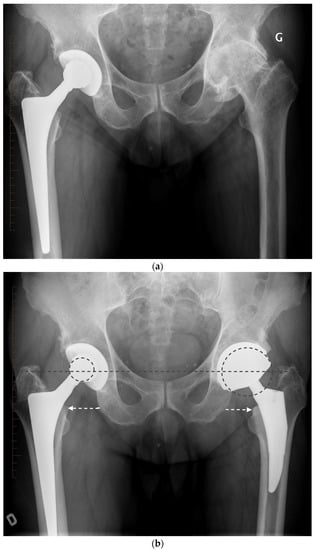

For the older, more sedentary patient or the patient with a shorter life expectancy, DM LDH THA is the ideal alternative (Figure 7 and Figure 8). DM implant design has the LDH stability benefits and wear rates significantly lower than fixed bearing implants [,]. Loving et al., in a simulator study, under multiple test conditions (impingement, abrasion, loss of mobility of the insert), showed that the performance in terms of wear was dictated mainly by the smaller articulation and by the polyethylene material used. For the most severe tests, a 75% lower wear rate was observed compared to a fixed insert of conventional polyethylene sterilized under gamma rays in an inert atmosphere []. Additionally, with osteopenic bone there is a higher risk of intra-operative periprosthetic fractures with LDH press fit monoblocks [,]. Bearing a lower cost and avoiding the potential drawbacks of hard-on-hard bearings (noise, fracture, and trunnionosis), DM should be considered for patients over 65 years.

Figure 8.

(a) Antero-posterior pelvis radiograph of an 82-year-old man with severe post-traumatic right hip osteoarthritis. The fracture and secondary degeneration modified native acetabular cavity orientation. Using a DM, LDH THA helped obtain a stable joint and may forgive potential surgical impressions. (b) Post-operative anteroposterior pelvis radiograph. (c) Lateral view of the reconstructed right hip.